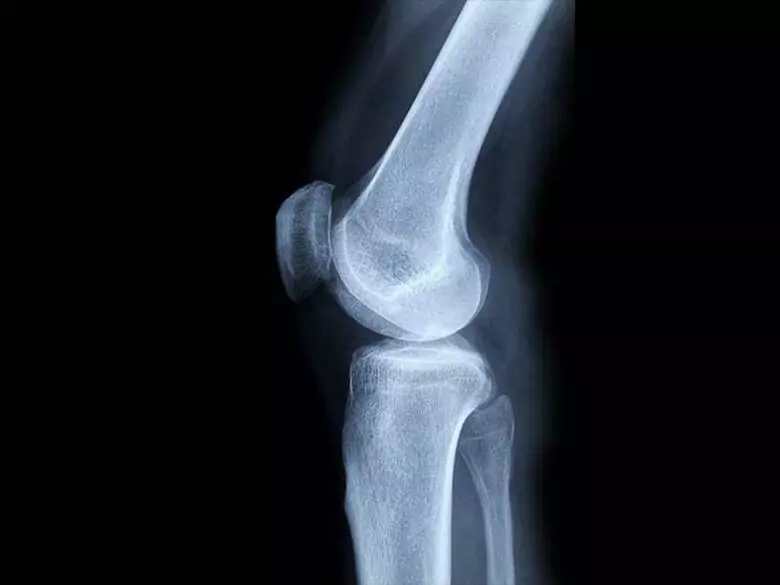

Bien qu'il ne s'agisse pas du type de cancer le plus courant, il s'agit d'une maladie très maligne qui se développe rapidement et donne des métastases. Les tumeurs osseuses malignes primaires sont difficiles à diagnostiquer. En raison de leur localisation et des causes connues, il n'est pas possible d'indiquer des mesures préventives.